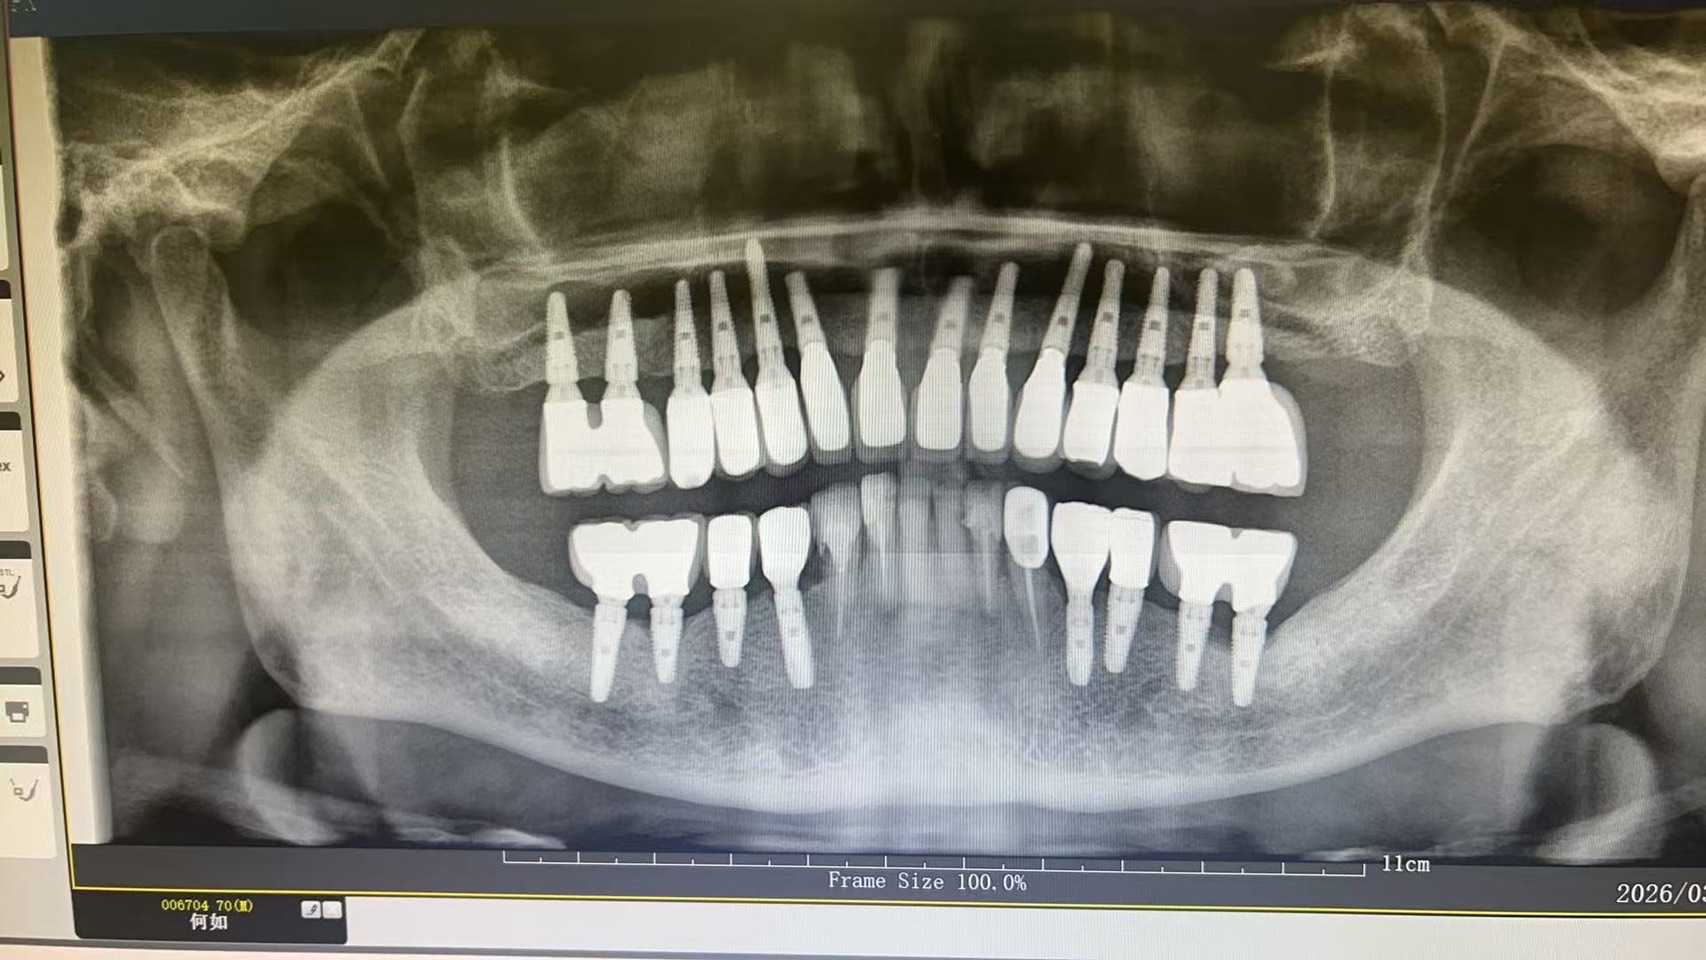

15年前植牙的案例

這位患者當年在美國接受植牙治療,之後因為工作與生活的關係來到中國,後來被陳博士在上海的一位學生看診時發現。

學生在檢查時看到這個植牙案例,覺得非常特別,於是拍了 X光片傳給陳博士,才讓這個 15年前的病例再次被看到。

即使已經過了 15年,從X光片來看,骨頭高度仍然維持得非常好,幾乎沒有明顯的 bone loss。

這樣的長期結果,其實正好體現了一個非常經典、也非常自然的修復理念:「一冠一釘」也就是 一顆牙齒,一根植體。

如果以全口來看(不含智齒),28顆牙齒對應28顆植體,其實是最符合自然牙齒排列的重建方式。